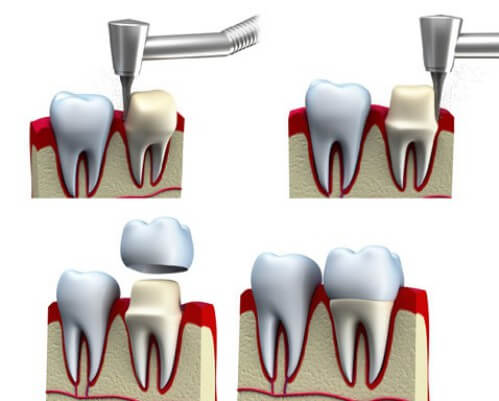

Răng sứ được phân chia thành hai loại: răng sứ kim loại và răng sứ toàn sứ.- Răng sứ kim loại được cấu tạo khung sườn là kim loại, hợp kim và được tráng một lớp ngoài cùng là sứ trắng. Răng sứ kim loại có tuổi thọ không cao bằng loại răng sứ toàn sứ, và sau một thời gian sử dụng thường có biểu hiện bị đen viền chân răng.

- Răng sứ toàn sứ được cấu tạo cả khung sườn và lớp ngoài đều bằng sứ. Răng sứ toàn sứ có tuổi thọ cao hơn răng sứ kim loại, tính thẩm mỹ cao hơn và chi phí cũng đắt đỏ hơn.

Có một số nguyên nhân làm răng sứ bị ê buốt sau phục hình như:- Kĩ thuật mài cùi răng không tốt của bác sĩ, làm ảnh hưởng đến tủy răng

- Bước gắn răng sứ và chỉnh hình không tốt, làm khớp cắn của răng sứ và răng thật không khớp, gây cảm giác cộm làm tổn hại đến răng sứ.